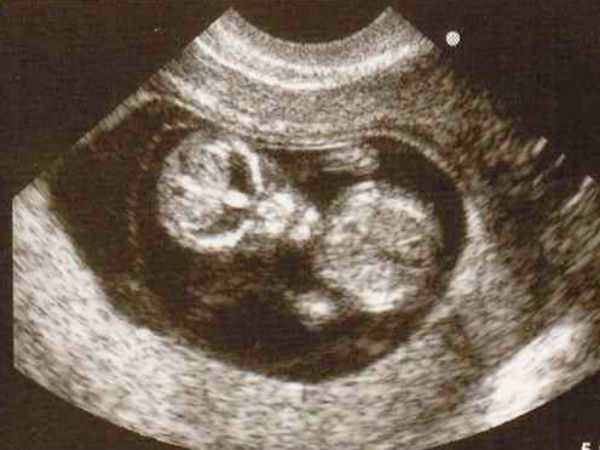

ಚಿತ್ರ#1 ಅನ್ಯಗ್ರಹದ ಮಗುವೇ ಇದು?

ಈ ಚಿತ್ರದಲ್ಲಿ ಕಾಣುವ ಮಗುವಿನ ಚಿತ್ರ ಯಥಾವತ್ತಾಗಿ ಒಂದು ಅನ್ಯಗ್ರಹ ಜೀವಿಯ ಮುಖದಂತೆ ಕಾಣುತ್ತಿದೆ ಅಲ್ಲವೇ? ಇದು ಎಷ್ಟು ನಿಜವಾಗುತ್ತದೆ ಎಂಬುದನ್ನು ಹೆರಿಗೆಯ ಬಳಿಕವೇ ಖಚಿತಪಡಿಸಬೇಕಷ್ಟೇ. ಈ ಮಗು ಎಲ್ಲರಂತೆ ಮುದ್ದು ಮುಖವನ್ನೇ ಹೊಂದಿರಲಿ ಎಂದು ನಾವೆಲ್ಲಾ ಹಾರೈಸೋಣ. ಈ ಚಿತ್ರವನ್ನು ಯಾವಾಗ ಮಹಿಳೆಯ ಸದಸ್ಯರೊಬ್ಬರು ತೆಗೆದು ಸಾಮಾಜಿಕ ತಾಣದಲ್ಲಿ ಪ್ರಕಟಿಸಿದರೋ, ಆಗಿನಿಂದ ಲಕ್ಷಾಂತರ ಮೊಬೈಲುಗಳಲ್ಲಿ ಇದು ಹರಿದಾಡುತ್ತಿದೆ.